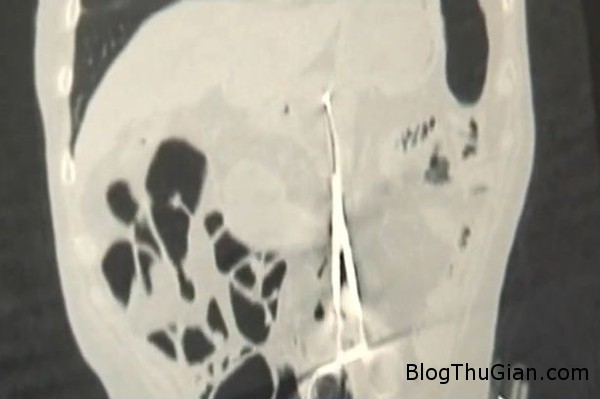

Chiếc kéo nằm trong dạ dày của ông Karp.

Cùng lúc đó, bác sĩ Baurzhan Aybaev, 44 tuổi, người kiểm tra phim chụp X-quang đã phát hiện ra vật lạ trong dạ dày ông Karp. Ban đầu, ông cứ nghĩ là một miếng gạc nhưng về sau mới nhận ra đó là dụng cụ y tế. Theo bác sĩ Baurzhan, trường hợp của ông Baurzhan rất hiếm gặp. Thông thường nếu có sơ suất như vậy thì bệnh nhân sẽ phát hiện ra sớm hơn.